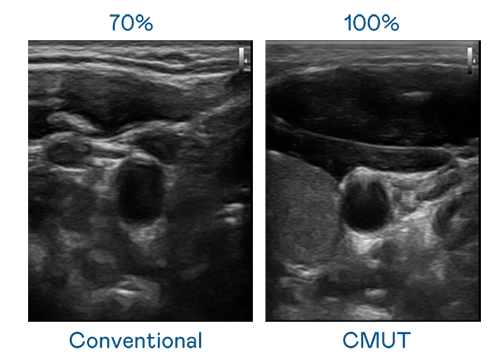

CMUT 技术是一种用电容式微机电元件来产生超音波讯号的技术。与传统 PZT 压电式技术相比,CMUT 频宽增加 30%,更宽频的超音波讯号让影像解析度大幅提升,是实现高影像品质医疗超音波扫描、促进精准医疗发展的关键技术。

超音波影像的解析度高低,首先取决于探头能发出的讯号频宽。AG百家乐试玩 CMUT 可提供高清晰的超音波讯号,提供高频宽、高灵敏度、影像纹理细节更高的超音波影像,协助医护人员缩短影像判读时间及利用精准的医疗影像进行诊断。